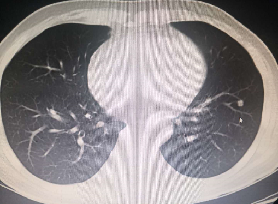

初治胸部CT(2017年12月)

2017年12月

化疗前